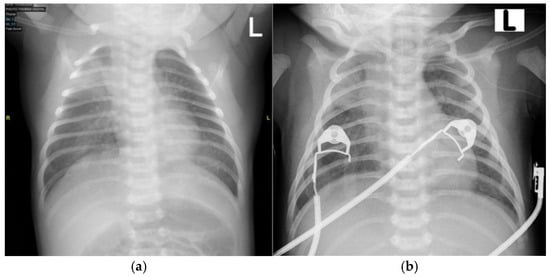

The patient was initially taken to a midwife and treated with a topical ointment, but the condition persisted. The patient was then brought to the secondary hospital where they were born and treated in the emergency department. As part of the initial therapy, the patient received intravenous ampicillin–sulbactam and gentamicin. The patient was subsequently referred to Hasan Sadikin General Hospital for further management (see Figure 2 for baseline chest X-ray taken on day 1 at the emergency department).

Figure 2. Anteroposterior (AP) chest X-ray on day 1 of admission to the emergency department (ED) showing normal cardiac and pulmonary structures with no abnormalities detected. “L”: an anatomical marker indicating the left side.